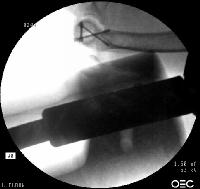

Screws were secured from the central articular component to the more proximal humeral cortices.

Click for larger image

These provided biplanar fixation, eventually with two screws in each direction.

The lateral column was then secured with two cannulated screws.